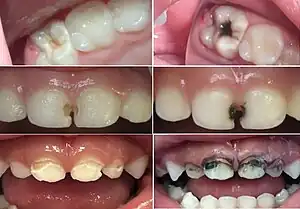

![]() Before (left) and after (right) use of SDF in people with tooth decay | |

| Side effects | Staining of cavities black, metallic taste[1] |

The main side effect of SDF is non-medical and is the prominent black staining of carious tooth tissue where the solution is applied.[24]